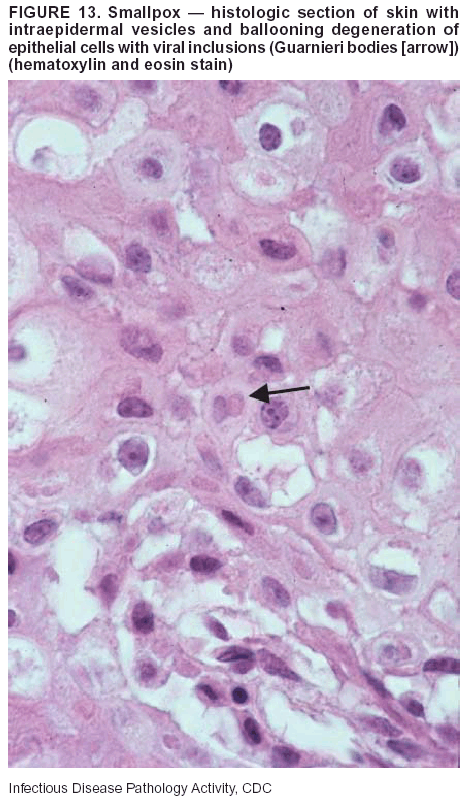

Pathologic Findings. Smallpox is an acute, highly contagious illness caused by a member of the Poxviridae family. Variola major refers to the form with a higher mortality rate, and variola minor or alastrim is a milder form. The lesions develop at approximately the same time and rate, starting in the palms and soles and spreading centrally; they first appear as macules and papules, and then progress to vesicles and umbilicated pustules (Figure 12), followed by scabs and crusts, and end as pitted scars. Occasionally, a hemorrhagic and uniformly fatal form occurs. This form has extensive bleeding into the skin and gastrointestinal tract and can be grossly taken for meningococcemia, acute leukemia, or a drug reaction (42). Microscopically, the skin exhibits multiloculated, intraepidermal vesicles; ballooning degeneration of epithelial cells; intracytoplasmic, paranuclear, and eosinophilic viral inclusions (i.e., Guarnieri bodies) (Figure 13); and occasionally intranuclear viral changes. Secondary infections (e.g., bronchitis, pneumonia, and encephalitis) can complicate the clinical appearance (43--48).

Diagnostic Tests. Electron microscopic studies of vesicle fluid or skin samples can identify characteristic viral particles (Figure 14). IHC studies have demonstrated the virus in the epithelial cells and in the subjacent fibroconnective tissue.